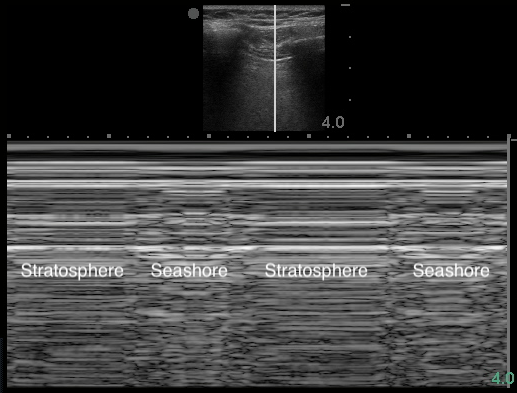

Pneumothorax

- Sonographic signs include:10,11

- Absence of lung sliding

- Figure 16. Stratosphere sign in M-mode

- Air within pleural space scatters the sound waves. The stationary parietal pleura attached to the chest wall is still visualized, but the visceral pleura is not.

- Highly sensitive but not specific for PTX11,58